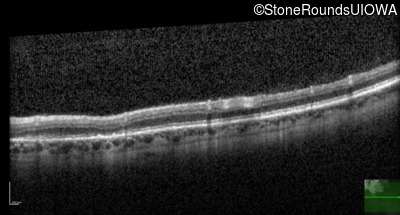

Optical Coherence Tomography - Left - 20/60 +2 sc

Exemplar / OCT Stack